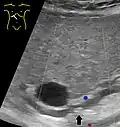

Abdominal ultrasonography of a common bile duct stone -